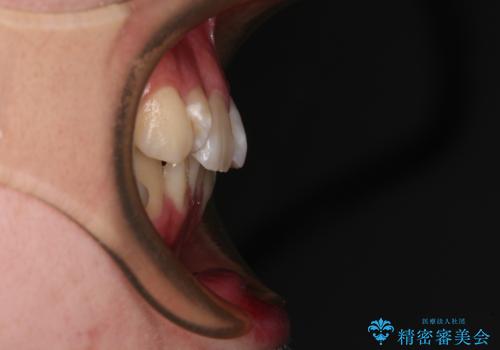

- 上下前歯のデコボコを気にして来院された患者様です。

口元の突出感はあまりなかったものの、デコボコを非抜歯で改善すると出っ歯になる可能性があるため、上下左右の第一小臼歯4本を抜歯し、ワイヤー装置にて矯正治療を行うこととしました。

口元の突出感はなかったものの、捻転や八重歯を改善するために補助装置を併用する必要がありました。